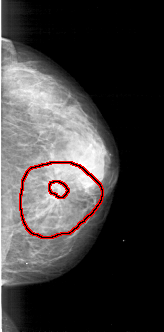

A_1835_1.RIGHT_MLO

FILE: A_1835_1.RIGHT_MLO.OVERLAY

TOTAL_ABNORMALITIES 1

ABNORMALITY 1

LESION_TYPE MASS SHAPE ARCHITECTURAL_DISTORTION MARGINS SPICULATED

ASSESSMENT 4

SUBTLETY 4

PATHOLOGY BENIGN

TOTAL_OUTLINES 2

BOUNDARY

CORE